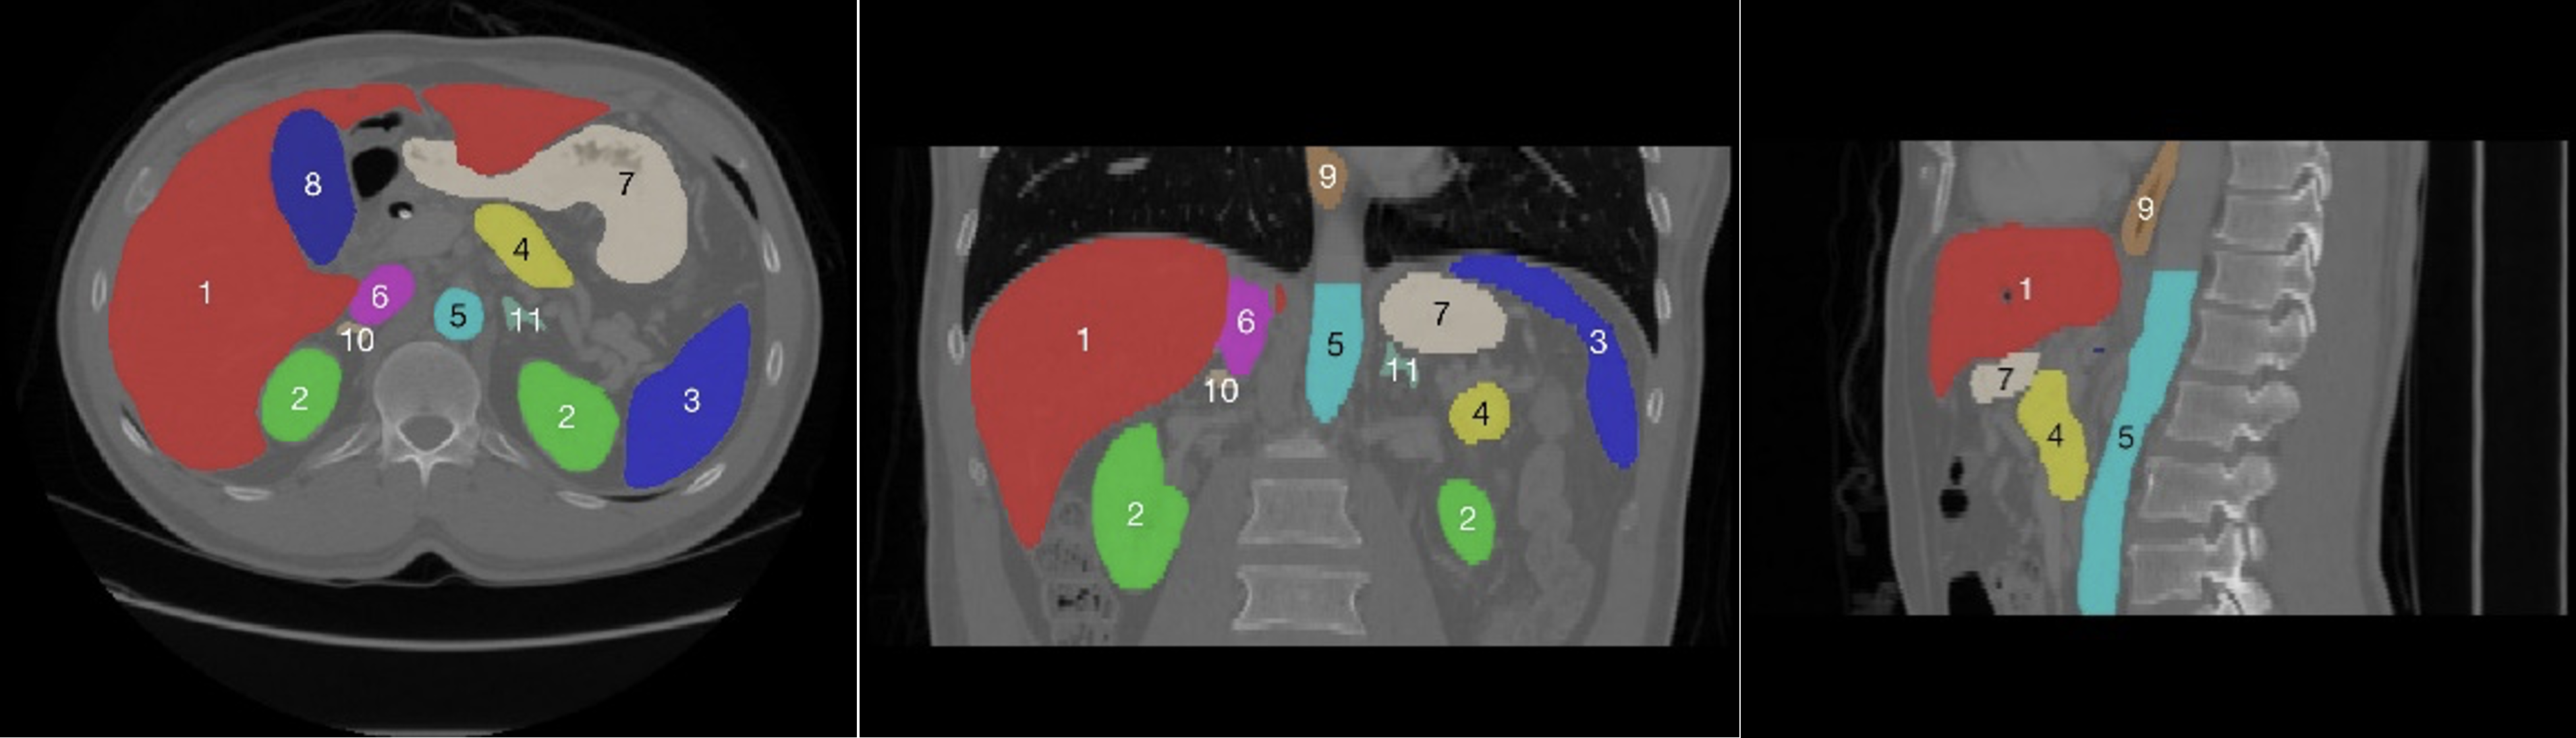

Using data-driven feature extraction approach and end-to-end training, the methods based on deep learning (DL) have been widely studied in the fields of image classification [21], object detection [22] and image segmentation [23, 24], image fusion [25], image registration [26], etc. The segmentation method based on deep learning has become a mainstream method in the field of medical image processing. However, there are two main difficulties in multi-organ deep learning segmentation tasks. First, as shown in the head and neck in Fig. 1, the abdomen in Fig. 2, the chest in Fig. 3, and the statistics of the multi-organ size in each part in Fig. 4, there are very large differences between the organs sizes, and the serious imbalances of different organs sizes will lead to a poor segmentation performance of the trained segmentation network for small organs. Second, due to the imaging principle of CT technology and the complex anatomical structure of the human body, the contrast between organs and their surrounding tissues is often low, which leads to the inaccurate segmentation of organ boundaries by segmentation networks. Therefore, it has become a new hot research topic to develop deep multi-organ segmentation methods that can accurately segment small and large organs at the same time.

The current multi-organ segmentation method is more effective in solving the segmentation of large organs and organs with standard contours, such as the brainstem and mandible in the head and neck; the left and right lungs and heart in the chest; and the liver, spleen, and stomach in the abdomen. Moreover, the DSC of various methods can basically reach 0.8 or higher, while for small organs, such as the optical chiasm in the head and neck (see Fig. 1(8)), the left and right optic nerves (see Fig. 1(6 and 7)), the DSC can only reach about 0.7; irregular organs such as the pancreas in the abdomen (Fig. 2(4)), and long striped organs such as the spinal cord (Fig. 2(6)), the segmentation results are also not very satisfactory. The future research direction is to enhance the segmentation accuracy of these types of organs using more advanced automatic segmentation frameworks.